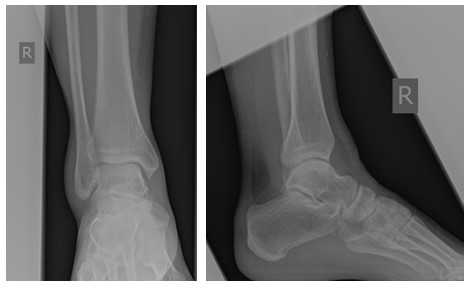

Клинический пример лечения застарелого разрыва передней таранно-малоберцовой связки, пяточно-малоберцовой связки правого голеностопного сустава у пациентки П.38 лет.

История неоднократных травм голеностопного сустава на протяжении более 10 лет, в среднем 2-3 раза в год подворачивает ногу, после чего наблюдается в травмпункте в связи с болями в голеностопном суставе. Обратилась к нам в клинику из-за того что после последнего эпизода подворачивания стопы боль держалась дольше обычного, и была более интенсивной. На стандартных рентгенограммах - без патологии.

На этом этапе пациентка лечилась по стандартному сценарию «растяжение голеностопа». Носила ортез, мазала голеностоп вольтареном и лиотоном, разгружала его при помощи трости. Но в связи с длительно сохраняющимся болевым синдромом было выполнено МРТ, при котором диагностирован застарелый разрыв передней таранно-малоберцовой связки, пяточно-малоберцовой связки правого голеностопного сустава, контузионное повреждение латеральных отделов таранной кости.